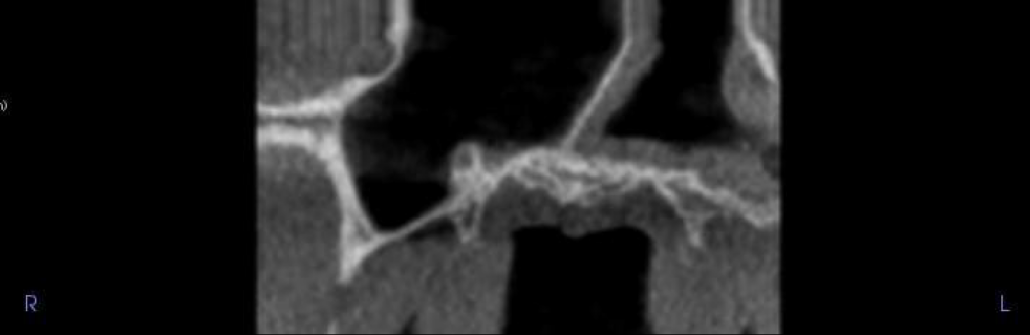

UL1 showing external root resorption, mostly on the palatal side of the root. Approximately a third to half of the root resorbed. The root may be partially ankylosed to the bone